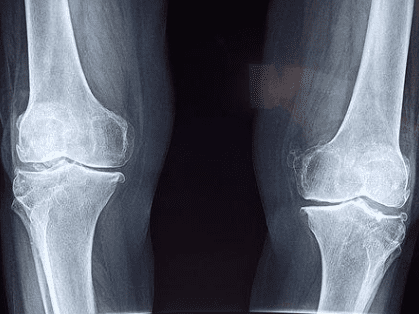

(2) 질환

인공관절치환술(슬관절) 인정기준에 준하는 질환자여야 합니다. 3개월 이상 병원에 내원하여 약물치료, 물리치료를 했음에도 불구하고 통증이나 증상이 지속되는 경우 인정 됩니다.

- 단순방사선이나 관절경 검사 등에서 관절연골 소실이 확인되어 치료가 힘든 퇴행성 관절염

- 만 60세 ~ 만 64세 이하 : Kellgren Lawrence grade 5 (퇴행성 관절염 5단계)

- 만 65세 이상 : Kellgren Lawrence grade 3단계 이상 - 타 수술(인대재건술 등)의 실패로 다발성 인대손상으로 인한 슬관절의 심한 불안정성